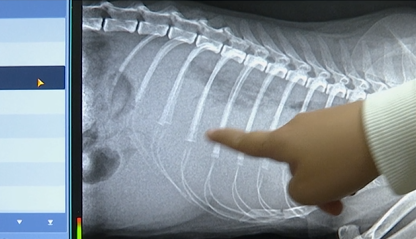

东方动物医院 负责人 王先生:这个是操作保定的正常手段,现在余女士质疑我们压得过紧包得过严,导致它的死亡,但是它的死亡我们也拍了片,也给余女士做了解释,她的猫咪是有胸水 ,是因为胸腔积液导致她猫咪死亡。

余女士:在抽血的过程中猫咪已经死亡了,而他们所谓的拍片已经是等到猫咪死亡两个小时以后才拍的,反咬我一口说是我家猫咪有病病死的。这样避而不见的态度,不管是拿起法律的武器保护自己,只要有一点点小小的希望,我都会全力以赴的去争取。